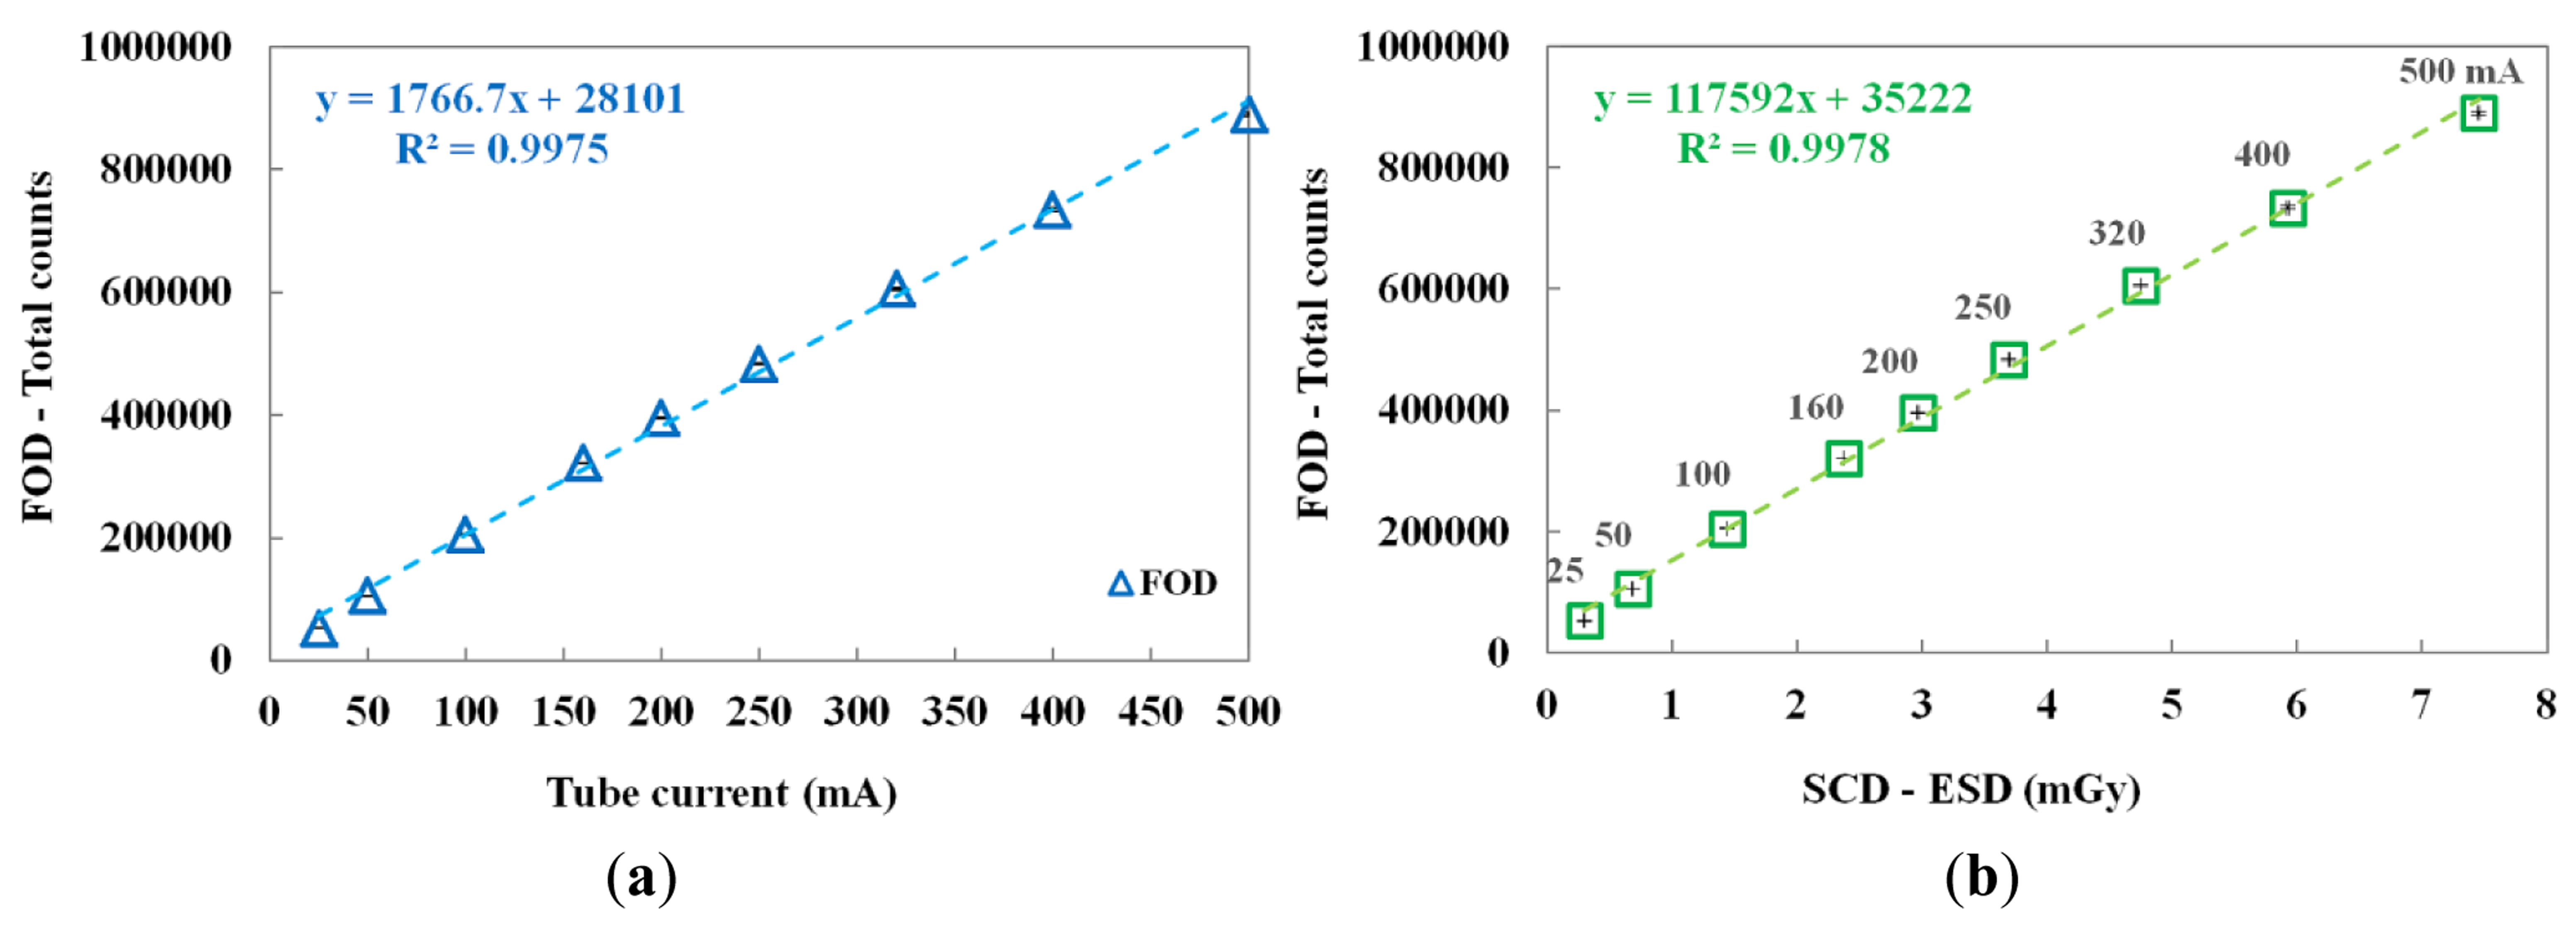

The performance of the FOD was evaluated by increasing the tube current from 25 to 500 mA. In this test, the irradiation time was fixed at 100 ms. Figure 5a,b shows the variation of total counts of the FOD according to the tube current and the relationship between the total counts of the FOD and the ESDs of the SCD at each tube current, respectively.

According to the increase of the tube current, both the total counts of FOD and the ESDs of the SCD linearly increased. Consequently, the proposed miniature FOD has a linear response with respect to the dose rate of the X-ray beam used in diagnostic radiology.